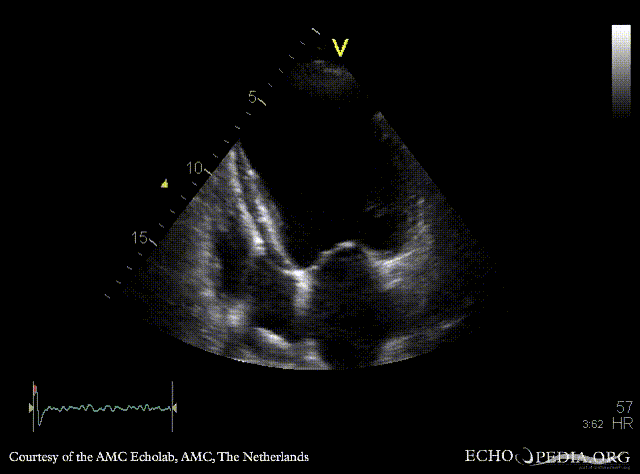

| Courtesy of: AMC Echolab, AMC, The Netherlands | |

| A4CH: apical aneurysm of left ventricle | A2CH: apical aneyrysm of left ventricle |